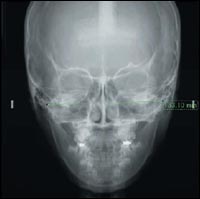

Цифровой дентальный рентгеновский аппарат Veraviewepocs cочетает в себе скорость с защитой для получения ярких и контрастных изображений, при этом время экспозиции составляет всего лишь 8,2 сек, что вдвое меньше времени экспозиции традиционных панорамных рентгеновских установок. Кроме низкой дозы облучения, стоматолог получает возможность легко управлять системой используя совершенно новые функции автоматической экспозиции и автофокусирования. Более того, с тех пор, как дентальный рентгеновский аппарат Veraviewepocs 5D дооснащается современным цифровым CCD сенсором для захвата изображений, больше нет необходимости в проявочном оборудовании для пленки, и уничтожении использованной пленки. Благодаря новейшей цифровой технологии дентальный рентгеновский аппарат Veraviewepocs отличается превосходной рабочей скоростью и безопасностью, далеко опережая по своим эксплуатационным качествам традиционные рентген оборудование.

Рентген оборудование компании J.Morita: эталон среди дентальных цифровых рентгеновских аппаратов Функция автоматической экспозиции обеспечивает прохождение рентгеновских лучей сквозь тело пациента и их обнаружение сенсорным датчиком. Затем компьютер использует данную информацию для синхронного управления напряжением и силой тока по отношению к скорости движения пленки. Это обеспечивает высокое качество изображения с постоянным уровнем оптической плотности для любого пациента от маленьких детей до людей преклонного возраста. Для получения панорамного изображения скорость движения пленки должна быть в три раза больше, чем при облучении области моляров в сравнении с облучением области резцов. Это означает, что оптическую плотность необходимо регулировать для поддержания ее на постоянном уровне и получения оптимальной контрастности. Система автоматической экспозиции AVS, разработанная компанией J.Morita справляется с этой задачей благодаря проводимой при помощи компьютера координации напряжения трубки, силы тока трубки и скорости движения пленки.

Рентген оборудование компании J.Morita: эталон среди дентальных цифровых рентгеновских аппаратов Режим автоматической фокусировки обеспечивает исключительно точное позиционирование пациента. Светочувствительный сенсор измеряет расстояние до области резцов пациента. Затем моноблок С-образной формы перемещается в оптимальное положение среза изображения. Пациенту не нужно двигаться или теряться в догадках. В результате получаются четкие изображения отличного качества.